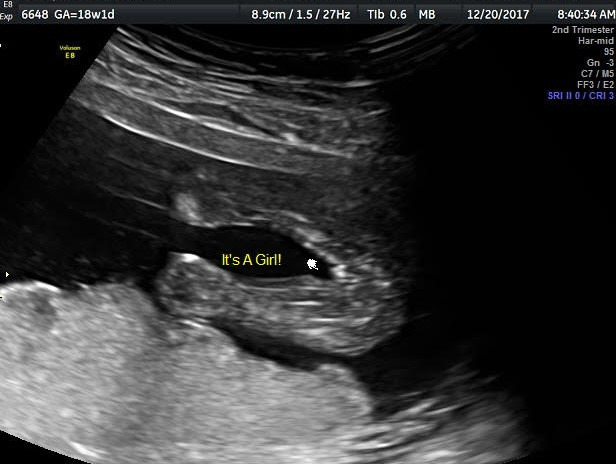

BABY_2.jpg 18주 차 초음파로 알게 된 너의 정체 :)